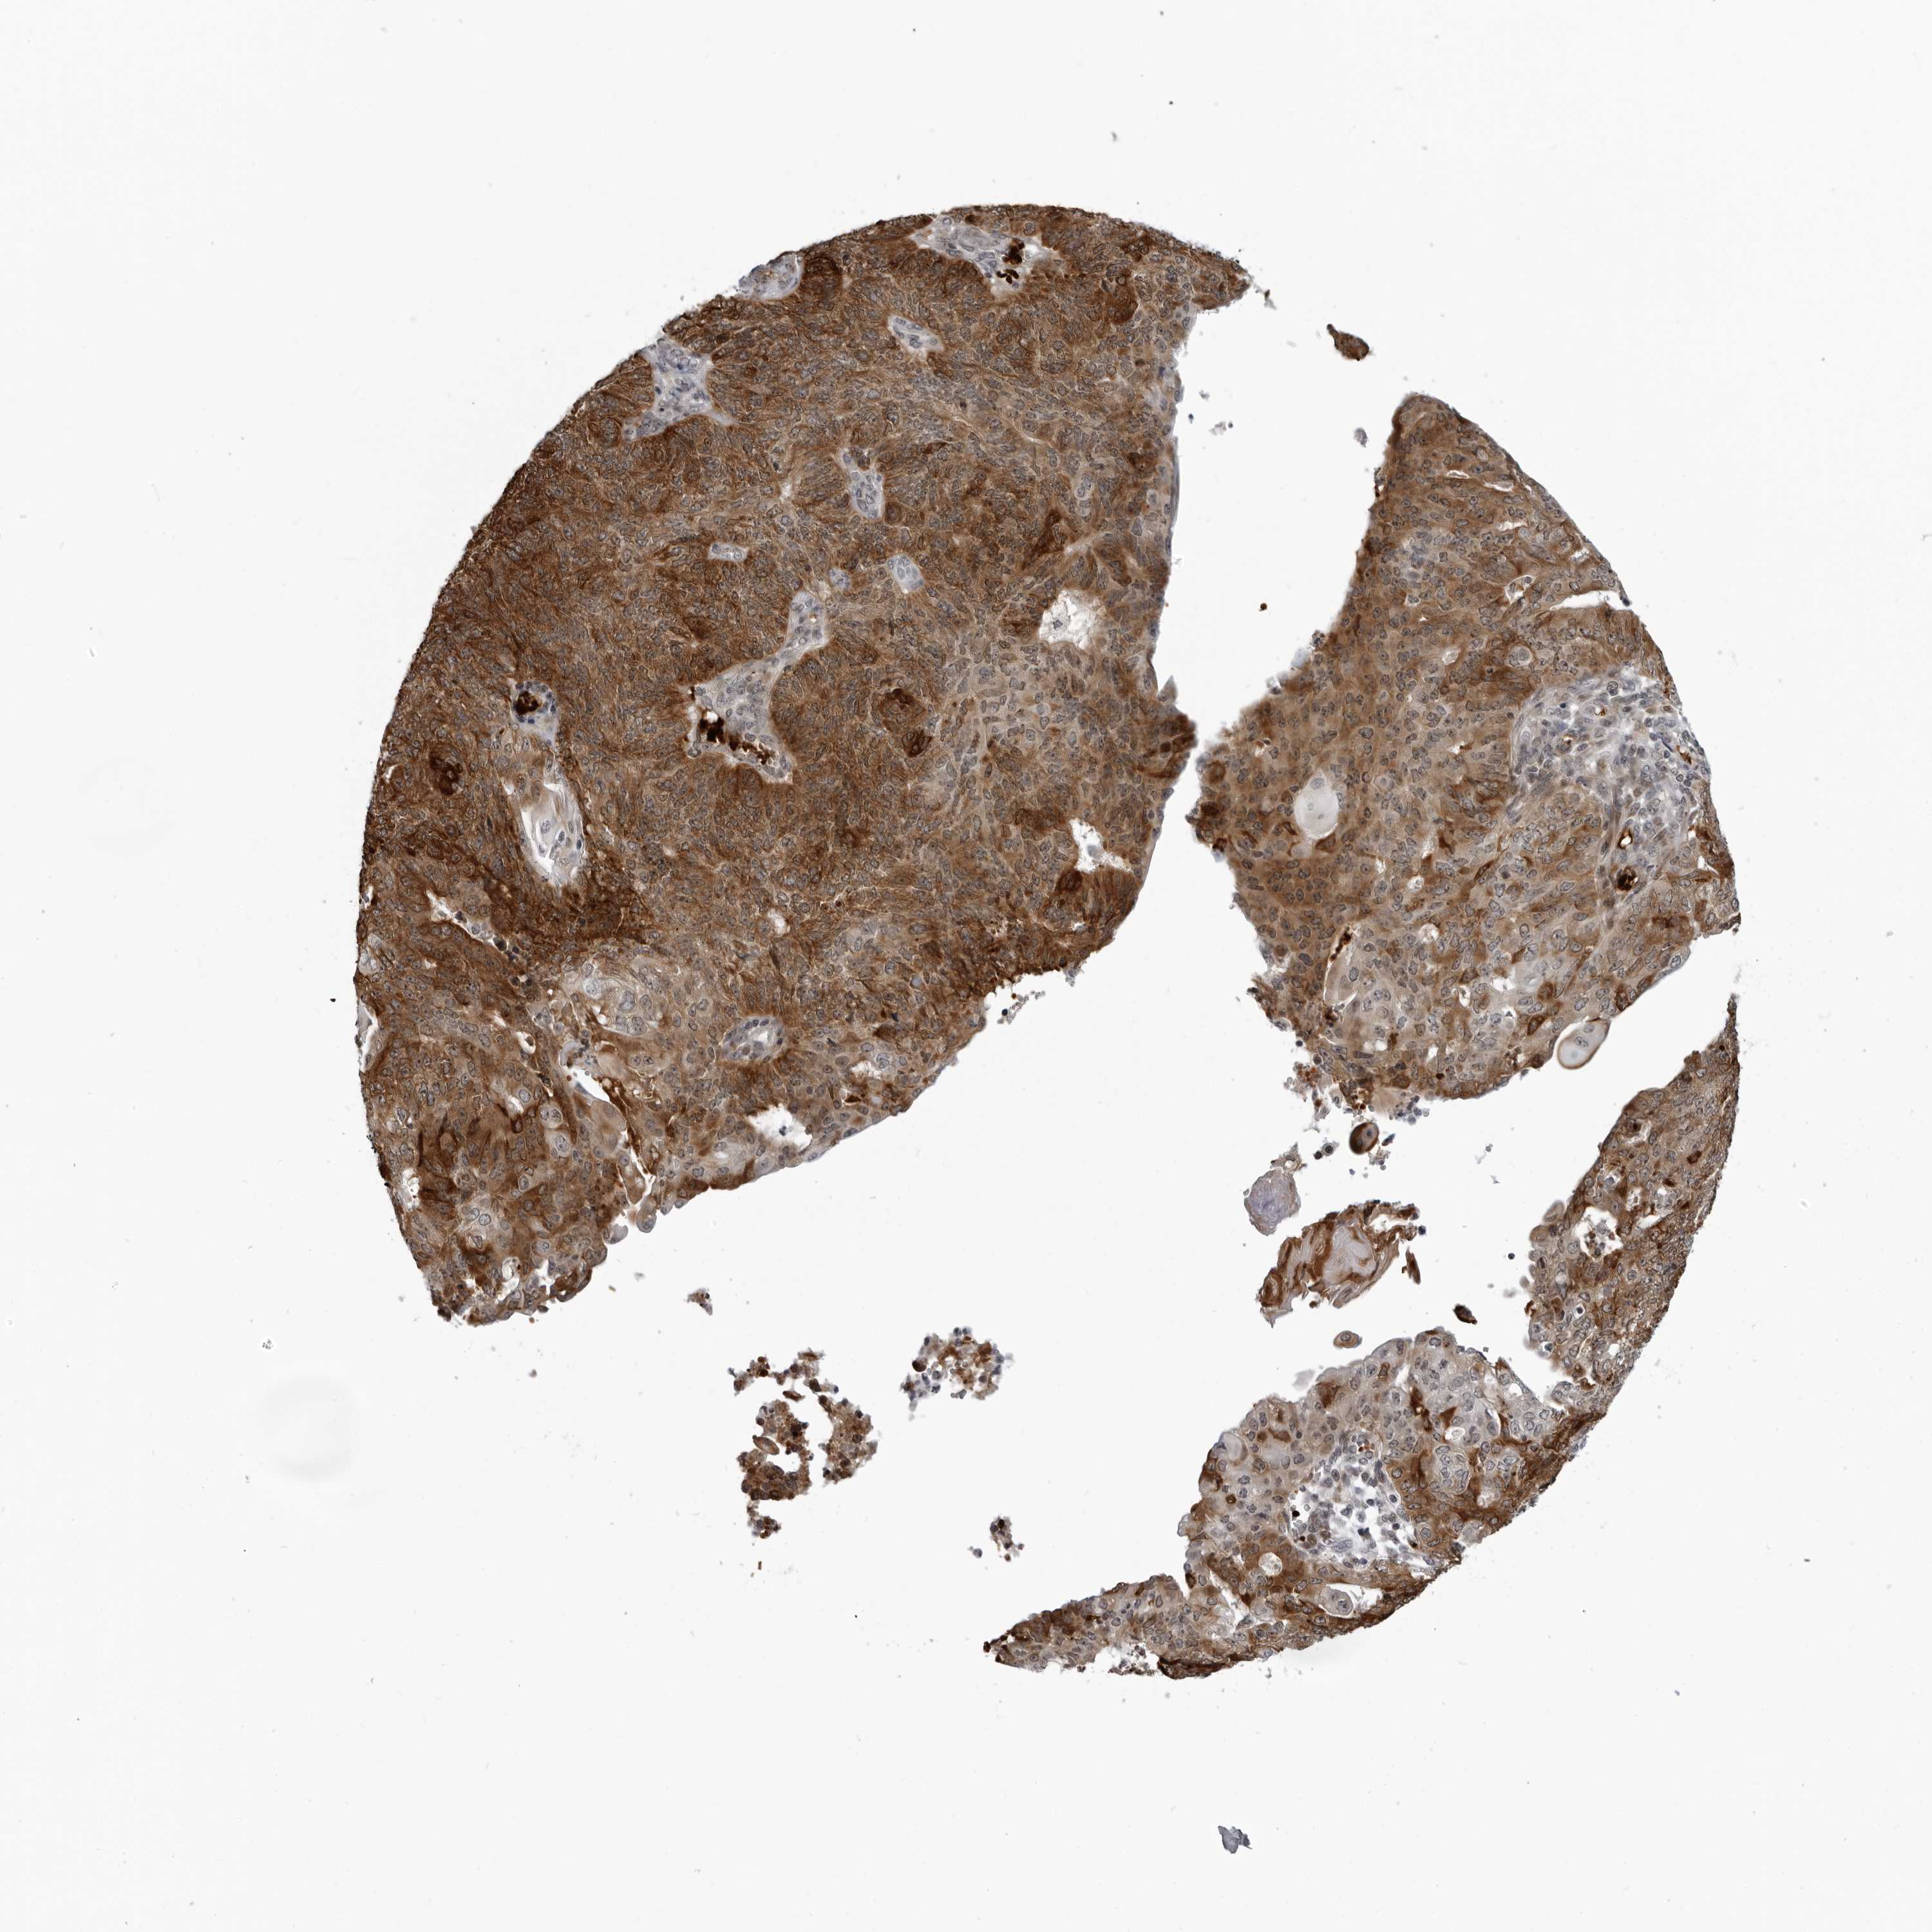

ENDOMETRIAL CANCER - Protein expressioni

A mouse-over function shows sample information and annotation data. Click on an image to view it in a full screen mode. Samples can be filtered based on level of antibody staining by selecting one or several of the following categories: high, medium, low and not detected. The assay and annotation is described here.

Note that samples used for immunohistochemistry by the Human Protein Atlas do not correspond to samples in the TCGA dataset.

Antibody stainingi

Antibody staining in the annotated cell types in the current human tissue is reported as not detected, low, medium, or high, based on conventional immunohistochemistry profiling in selected tissues. This score is based on the combination of the staining intensity and fraction of stained cells.

Each image is clickable and will lead to virtual microscopy that enables deeper exploration of all samples and also displays staining intensity scores, fraction scores and subcellular localization as well as patient and tissue information for each sample.

Antibody HPA035262

Antibody CAB025497

Staining

High

Medium

Low

Not detected

Intensity

Strong

Moderate

Weak

Negative

Quantity

>75%

75%-25%

<25%

None

Location

Nuclear

Cytoplasmic/membranous

Cytoplasmic/membranous,nuclear

Adenocarcinoma, NOS

Adenocarcinoma, metastatic, NOS